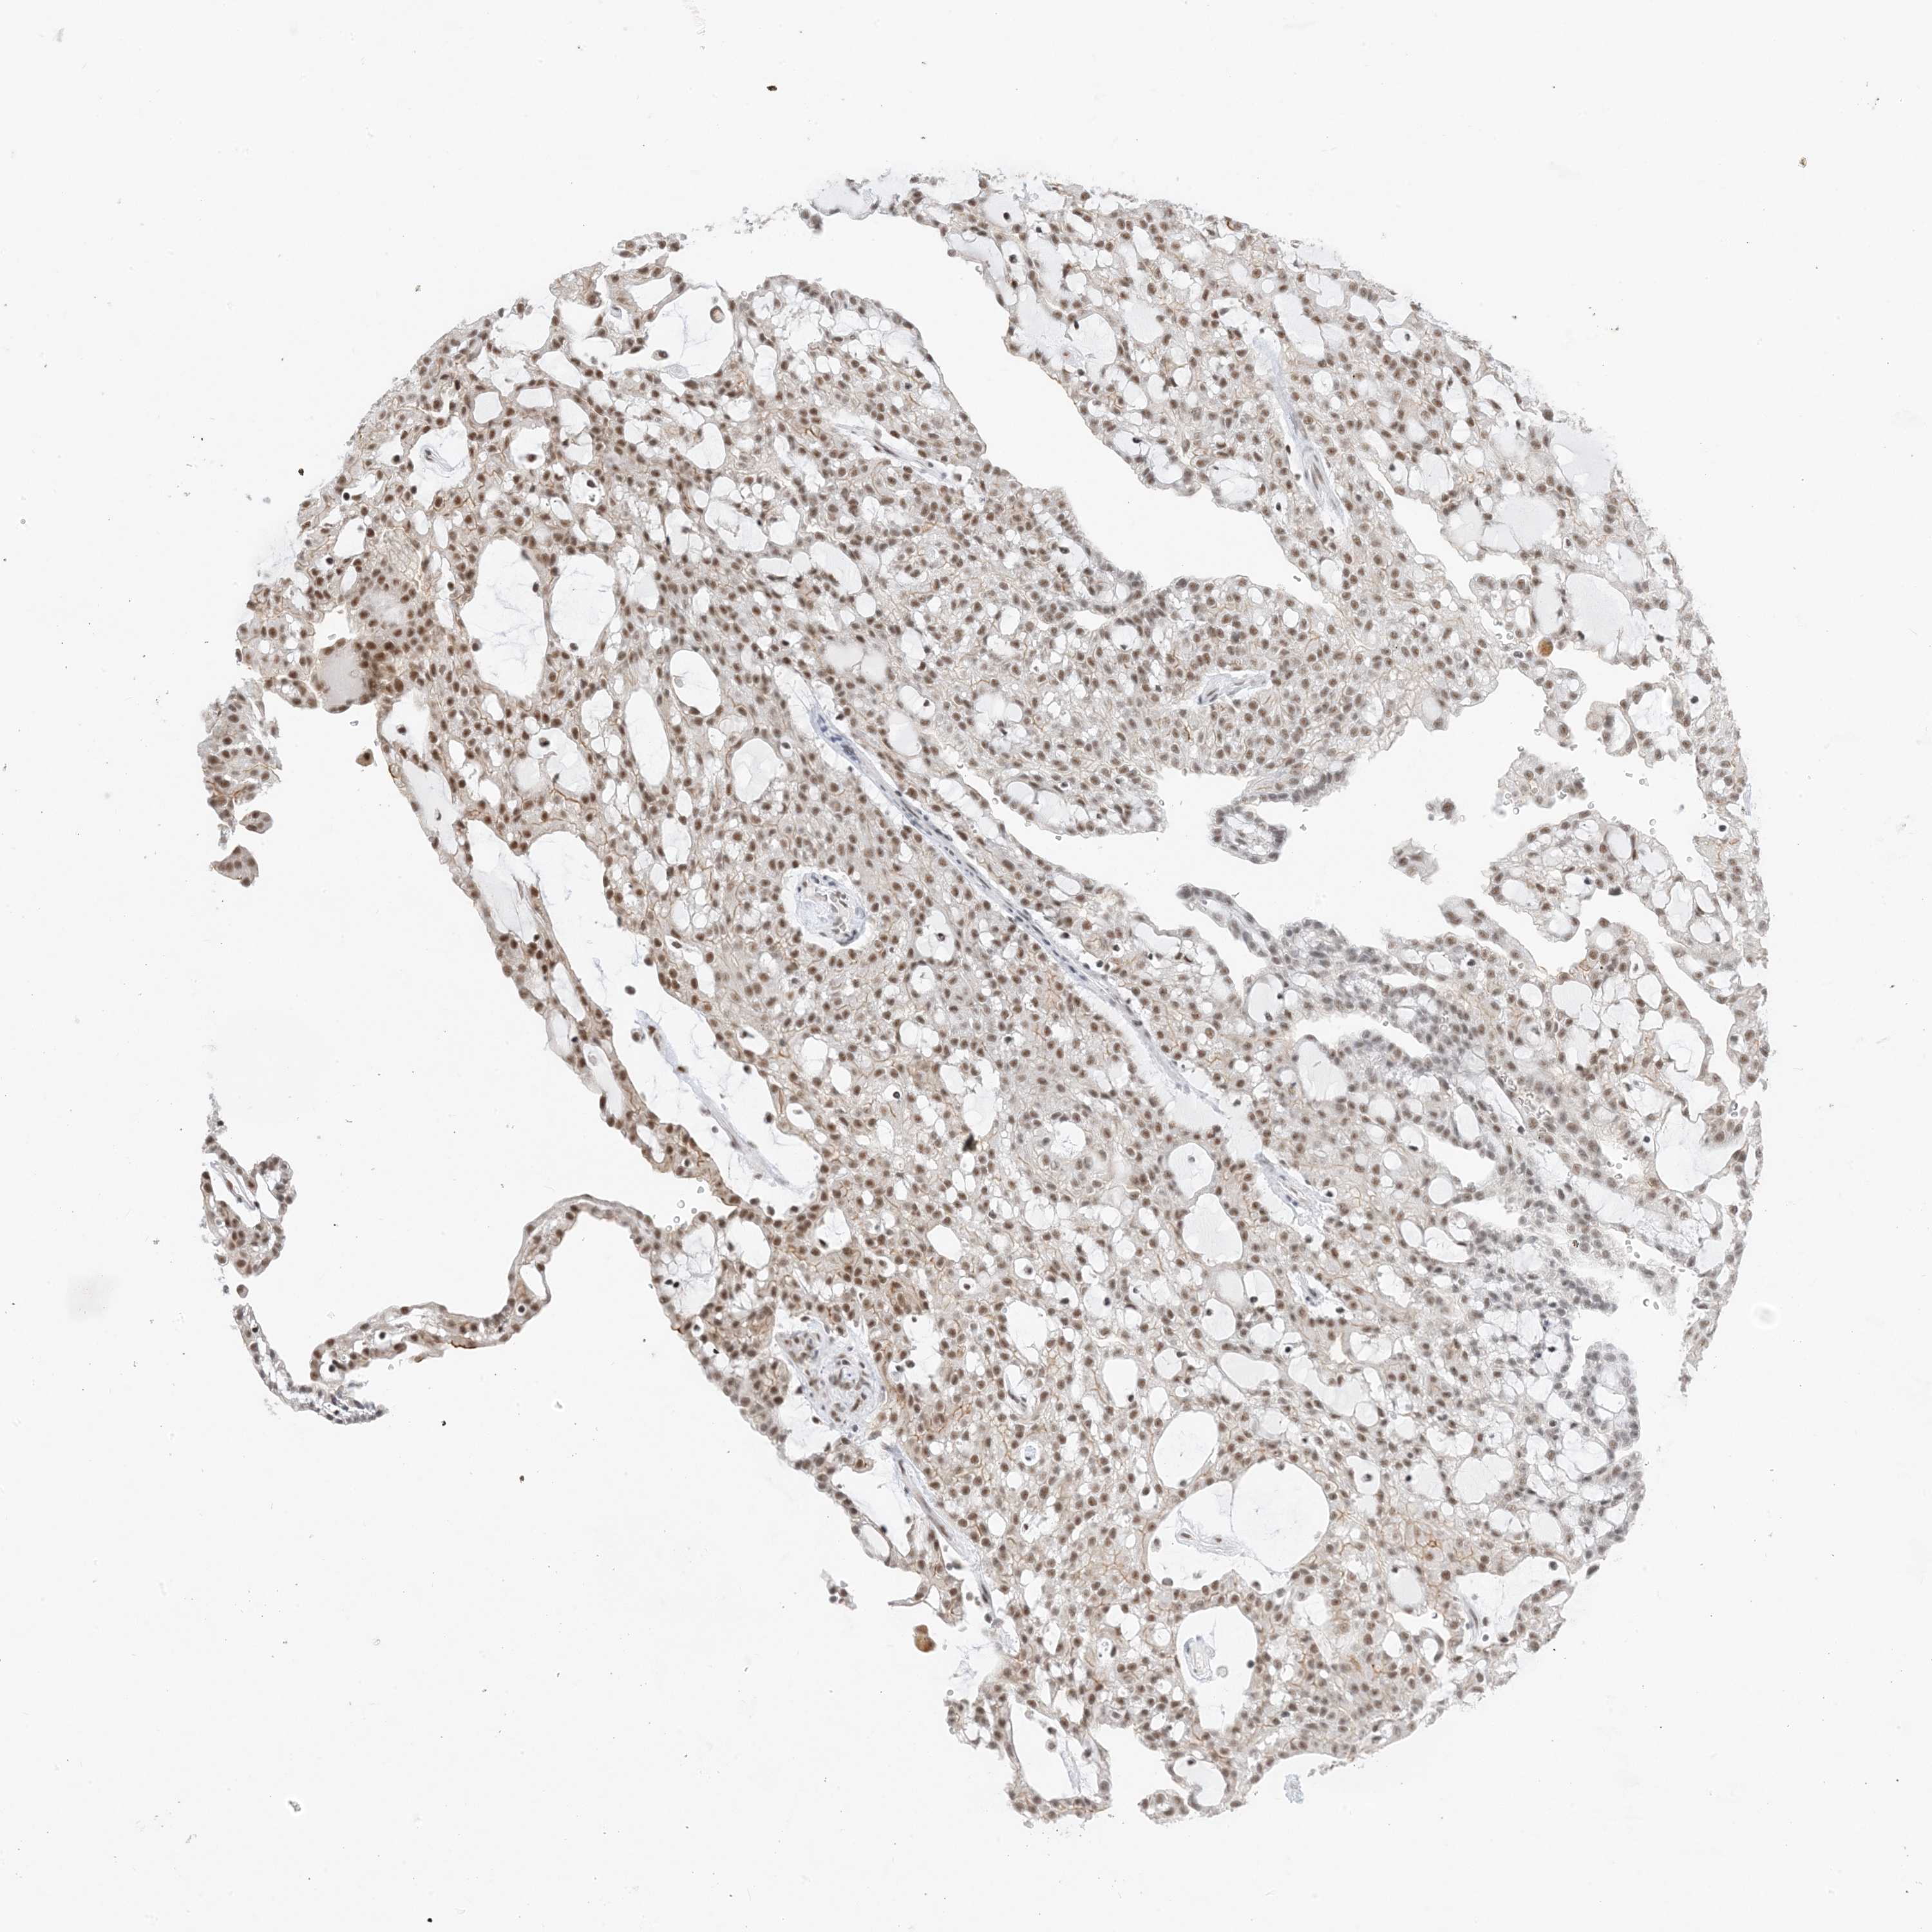

KIDNEY RENAL CLEAR CELL CARCINOMA (TCGA) - Interactive survival scatter ploti

SF3A3 is potential prognostic, high expression is favorable in Kidney Renal Clear Cell Carcinoma (TCGA)

: 26.64

Average pTPM 35.7

Number of samples 521